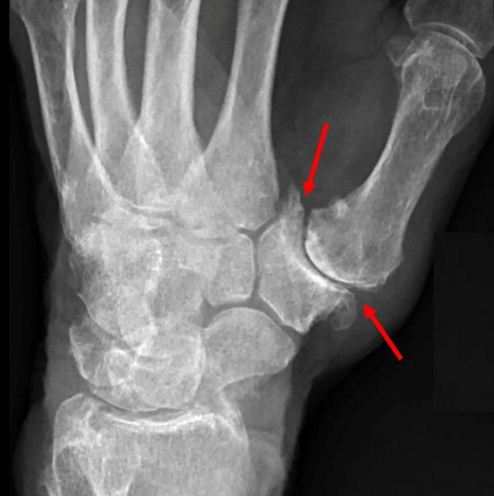

基底關節炎(basal joint arthritis),是一種發生在手上的退化性關節炎,發生位置是於手掌的大拇指「腕掌關節的骨關節炎(carpometacarpal joint arthritis)」。通常發生於中年女性。病患會有大拇指基部疼痛、僵硬、大拇指基部附近的壓痛及腫脹,嚴重的病症會影響拇指活動角度,拇指無力,而更甚著會有關節變形的狀況。

病因通常會是因為過度使用,進而使基底關節的軟骨磨損,及基底關節旁的韌帶鬆馳弱化。有些病患曾經發生車禍或是外傷,也會有類似的症狀。

治療上,初期的病患經過充份休息及拇指加強型護具固定,大多會自行緩解,配合復健及使用消炎藥物緩解疼痛。但倘若關節發炎至退化的程度,基底關節開始出現腫脹、變型或突出等狀況影響到日常生活,如寫字、抓握動作無力,此時的基底關節炎可能已發展至後期,更嚴重者會有疼痛加劇,疼痛影響睡眠及生活品質,就可能要進一步接受局部注射或手術治療。

手術治療方式會根據病患的年齡及嚴重度而調整,包括微創關節鏡手術、關節融合、大多角骨切除合併韌帶重建或人工韌帶懸吊,人工關節置換等等。

2010年美國史丹佛大學Jeffrey Yao教授發表了縫線鈕扣懸吊(suture button suspensionplasty)的手術方式治療基底關節炎,利用懸吊固定掌骨進一步增加關節穩定度,配合關節鏡微創手術進行。研究發現懸吊手術術後的復原較快,大拇指活動度及病人滿意度都相當高。